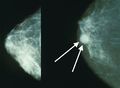

يتضمن الفحص السريري أو الذاتي للثدي تحسس الثدي للوقوف على وجود كتل أو أي تشوهات أخرى. يتم إجراء فحوصات الثدي السريرية من قبل مقدمي الرعاية الصحية، بينما تُجرى فحوصات الثدي الذاتية من قبل الشخص نفسه.[109] لا تدعم الأدلة فعالية أي من نوعي فحوصات الثدي، لأنه بحلول الوقت الذي يصبح فيه الورم كبيرًا بما يكفي ليتم اكتشافه، من المحتمل أن ينمو لعدة سنوات وبالتالي يصبح كبيرًا بما يكفي ليتم لاكتشافه بدون فحص.[110][111] يستخدم فحص التصوير الإشعاعي لسرطان الثدي بالأشعة السينية لفحص الثدي بحثًا عن أي كتل. أثناء الفحص، يتم ضغط الثدي ويلتقط الفني صورًا من زوايا متعددة. يلتقط التصوير الشعاعي للثدي العام صورًا للثدي بأكمله، بينما يركز تصوير الثدي الشعاعي التشخيصي على كتلة معينة أو منطقة معينة مثيرة للقلق.[112]

يمكن أن توفر طريقتا الفحص الأكثر شيوعًا، وهما الفحص البدني للثدي بواسطة مقدم الرعاية الصحية والتصوير الإشعاعي للثدي، احتمالًا تقريبيًا لوجود كتلة سرطانية، وقد تكتشف أيضًا بعض الآفات الأخرى، مثل الكيسات البسيطة.[122] عندما تكون هذه الفحوصات غير حاسمة، يمكن لمقدم الرعاية الصحية أخذ عينة من السائل الموجود في الكتلة لتحليلها مجهريًا (إجراء يُعرف باسم الخزعة بالإبرة) للمساعدة في تحديد التشخيص. يمكن إجراء الخزعة بالإبرة في عيادة أو مكتب مقدم الرعاية الصحية. يمكن استخدام مخدر موضعي لتخدير أنسجة الثدي لمنع الألم أثناء العملية، ولكن قد لا يكون ضروريًا إذا لم يكن الورم تحت الجلد. إن اكتشاف وجود سائل واضح يجعل الكتلة غير سرطانية إلى حد كبير، ولكن قد يتم إرسال السائل الدموي للفحص تحت المجهر بحثًا عن الخلايا السرطانية. يمكن استخدام الفحص البدني للثدي، والتصوير الشعاعي للثدي، والخزعة بالإبرة معاً لتشخيص سرطان الثدي بدرجة جيدة من الدقة.

سرطان القنوات الغازية عالي الجودة، مع الحد الأدنى من تكوين الأنابيب، ووضع علامة تعدد الأشكال، وانقسامات بارزة، المجال 40x.

تصوير الثدي يظهر ثدياً طبيعياً (اليسار) وثدياً مصاب بالسرطان (اليمين).